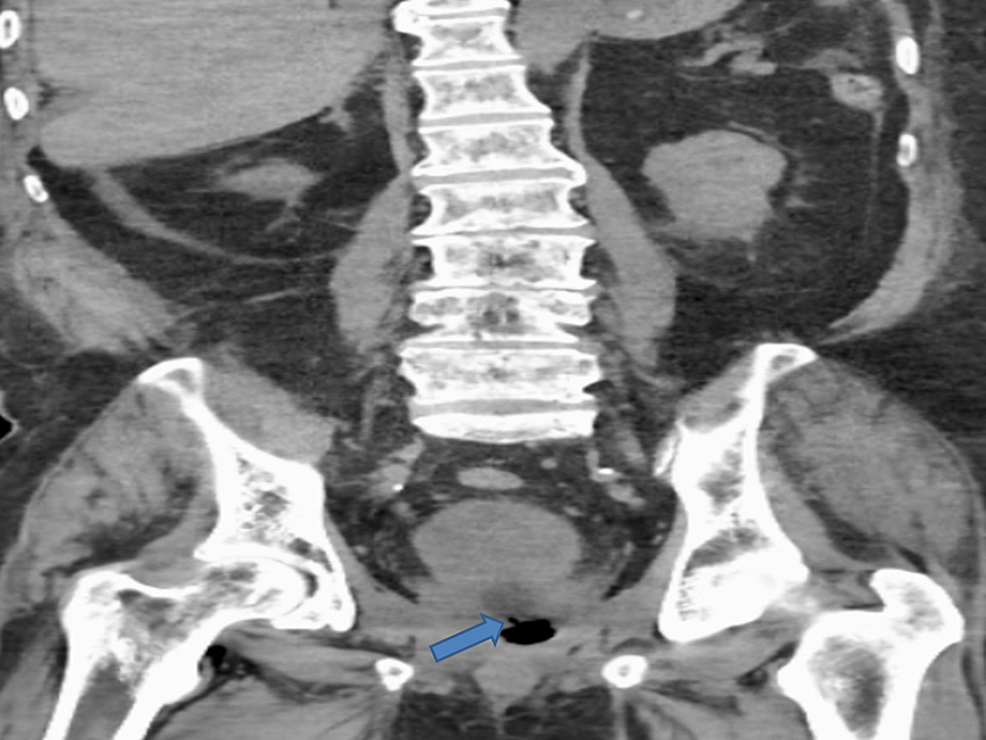

An 82-year-old male with a history of type 2 diabetes mellitus, hypertension, benign prostatic hyperplasia (BPH) with a size of 40 gram presented with asthenia, suprapubic pain, and distension of the lower abdomen. He underwent transurethral resection of prostate (TURP) for his BPH one week prior to admission and had an indwelling Foley’s catheter (due to urinary incontinence) at presentation. He also complained of non-bloody, watery diarrhea with four to five episodes per day for five days. He denied fever, cloudy urine, purulent urethral secretion, or any back pain. He also denied any prior history of radiotherapy or other gastrointestinal (GI) surgery related to the colon. At presentation, the patient was alert, awake, and cooperative and his vital signs included a temperature of 98.6° F, respiratory rate of 14 per minute, pulse of 86 beats per minute, BP of 113/56 mm Hg, and saturating 99% in room air. The physical examination revealed an indwelling Foley catheter with an attached right thigh bag showing clear urine. Laboratory investigations were notable for a slight elevation of the creatinine from the baseline. The urinalysis was positive for leukocyte esterase and nitrates, five to 15 red blood cell/high power field (HPF), and 30-50 white blood cell/HPF. The stool culture revealed no growth of microorganisms. The patient was started on intravenous (IV) normal saline and IV ceftriaxone 1 gram daily for a suspected urinary tract infection. Computed tomography (CT) of the abdomen and pelvis with IV contrast demonstrated findings consistent with a RUF. Cystourethrogram under fluoroscopy showed the extravasation of contrast into the rectum, which is also consistent with a rectourethral fistula (RUF) (Figure 1).

The abdominal and pelvic CT scan also showed RUF (Figures 4-5).